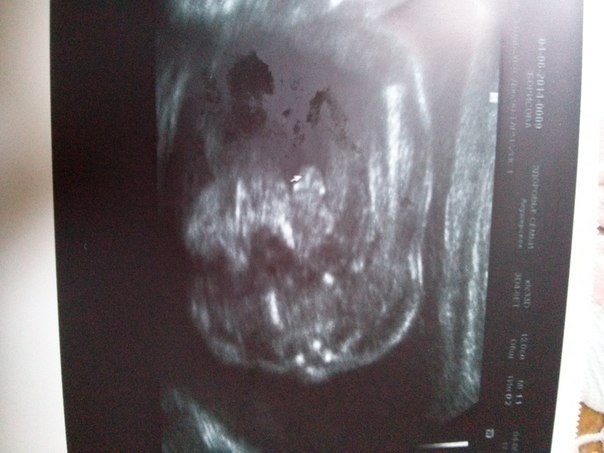

Про малыша. Его движения всё чётче и сильнее. На УЗИ мы были ровно в 22 недели. Пол малыша нам подтвердили. Но наш Папочка, который присутствовал, сказал, что нам важнее, что с ребёночком всё в порядке. По УЗИ срок даже больше, чем по месячным. Опережает на 2-3 дня. Так - всё в пределах нормы. Нам сделали фото личика и писюна на память)))